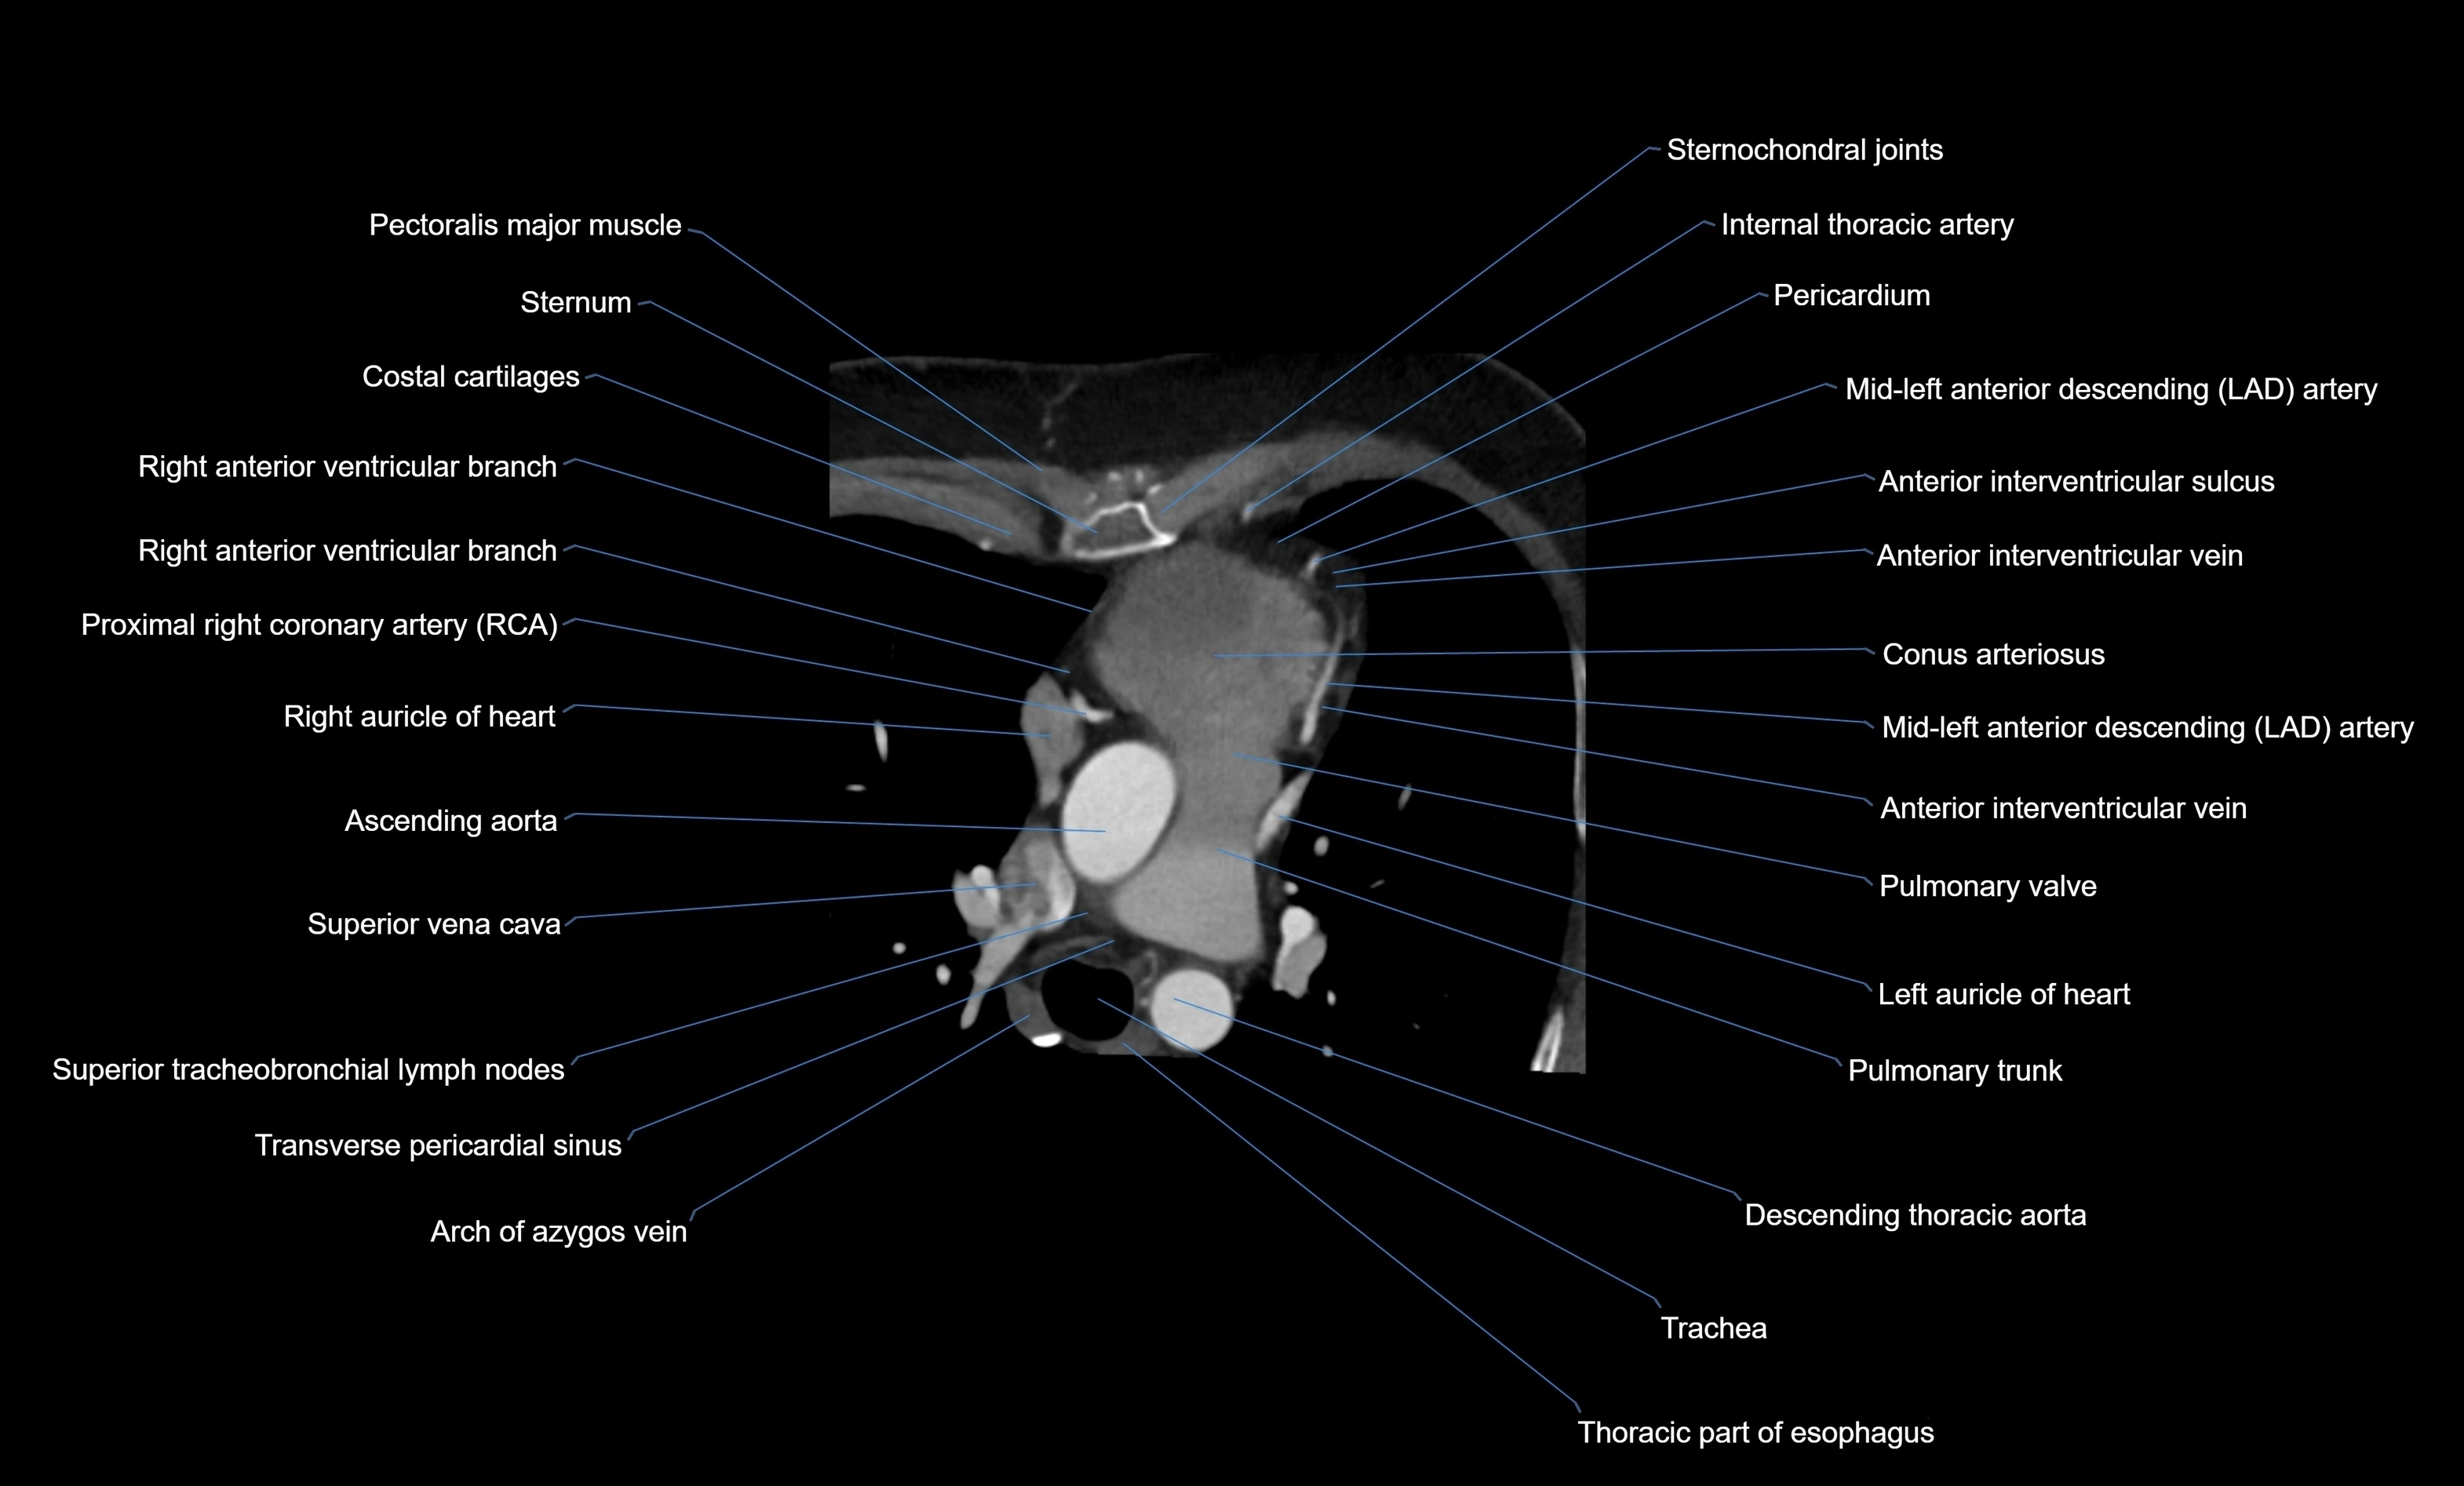

CT images